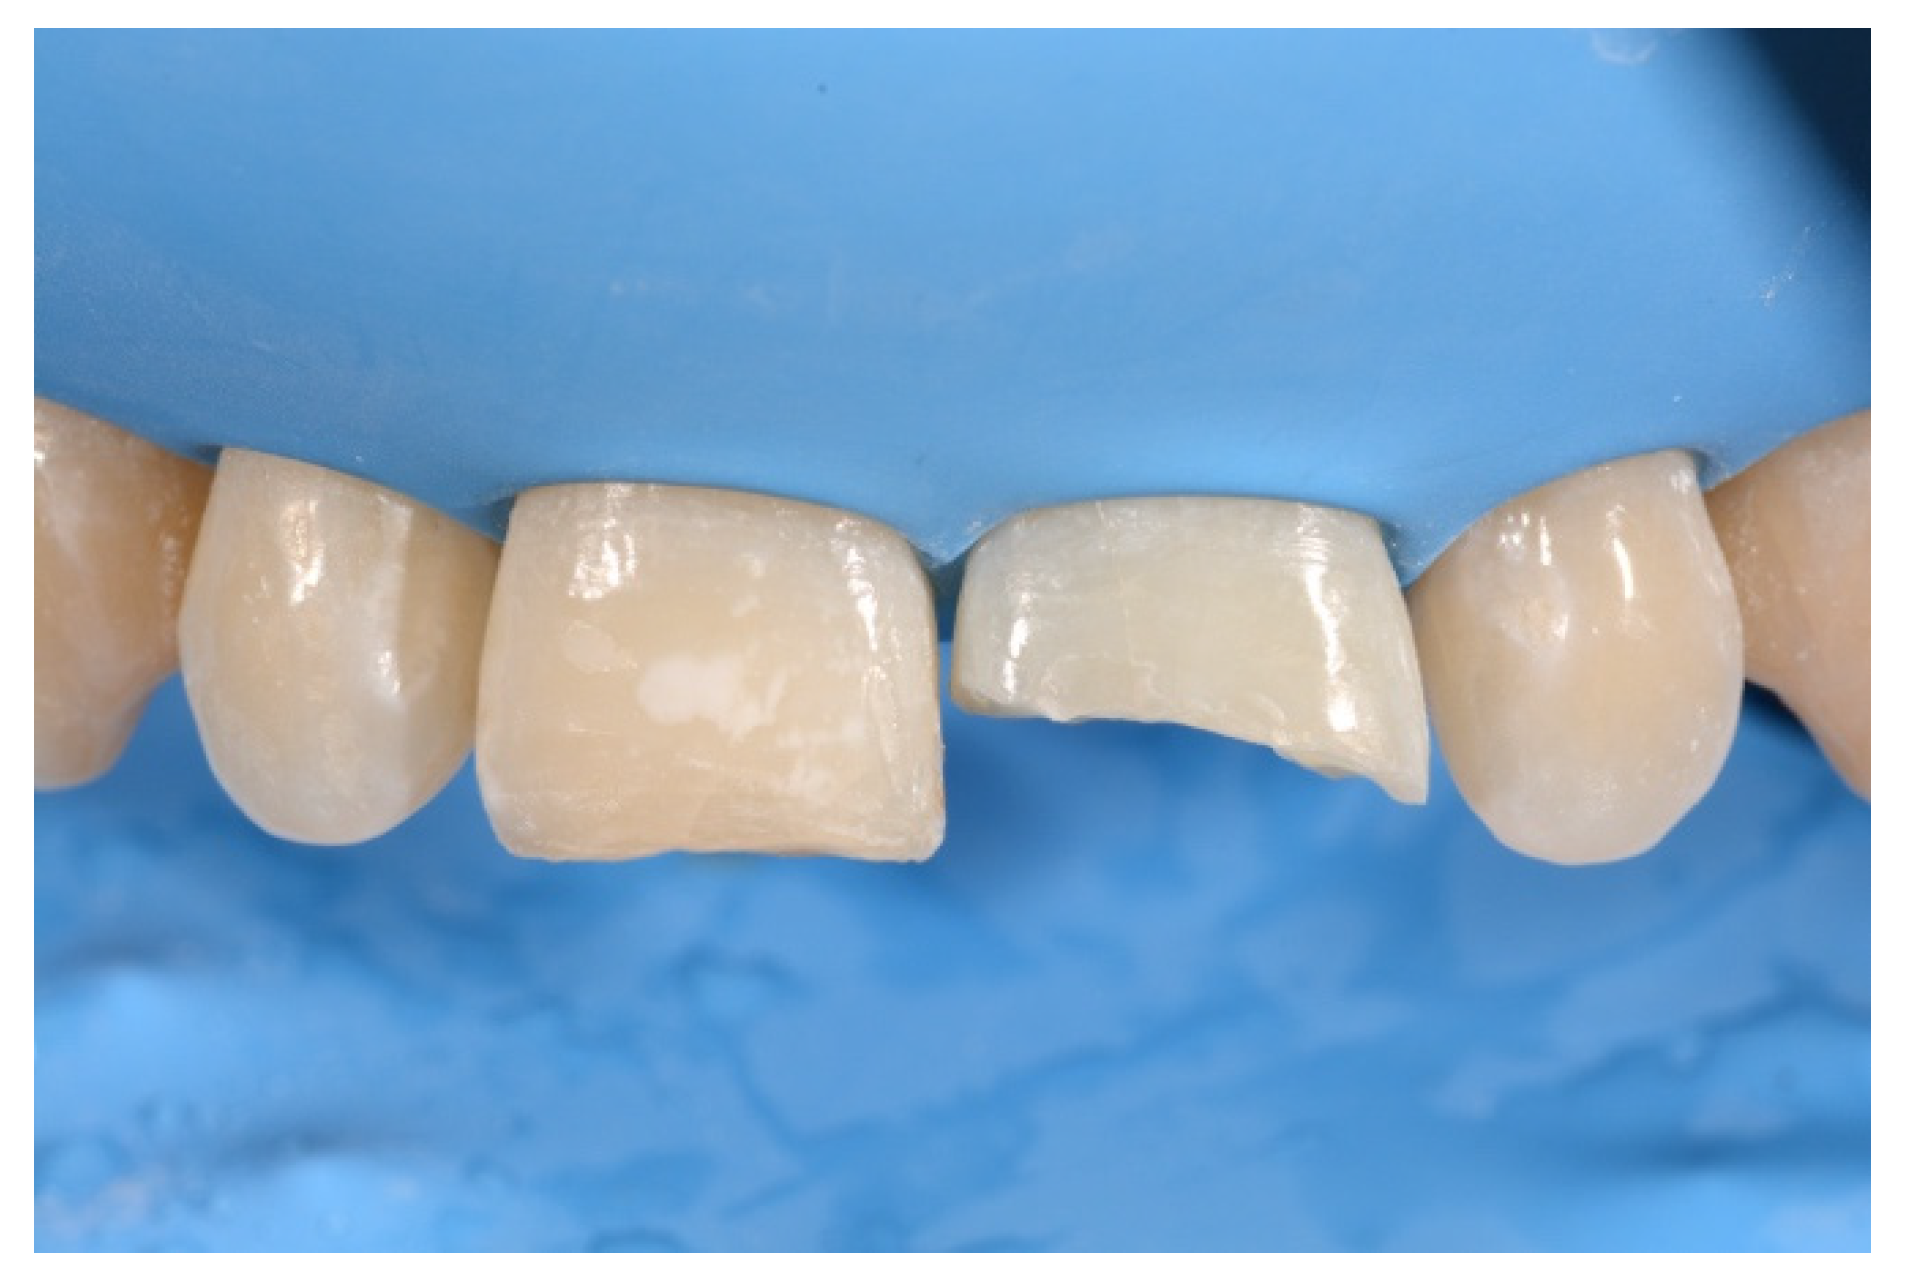

2. Case Presentation

- Building interproximal walls with matrices;

- Layering free-hand buccal surface.